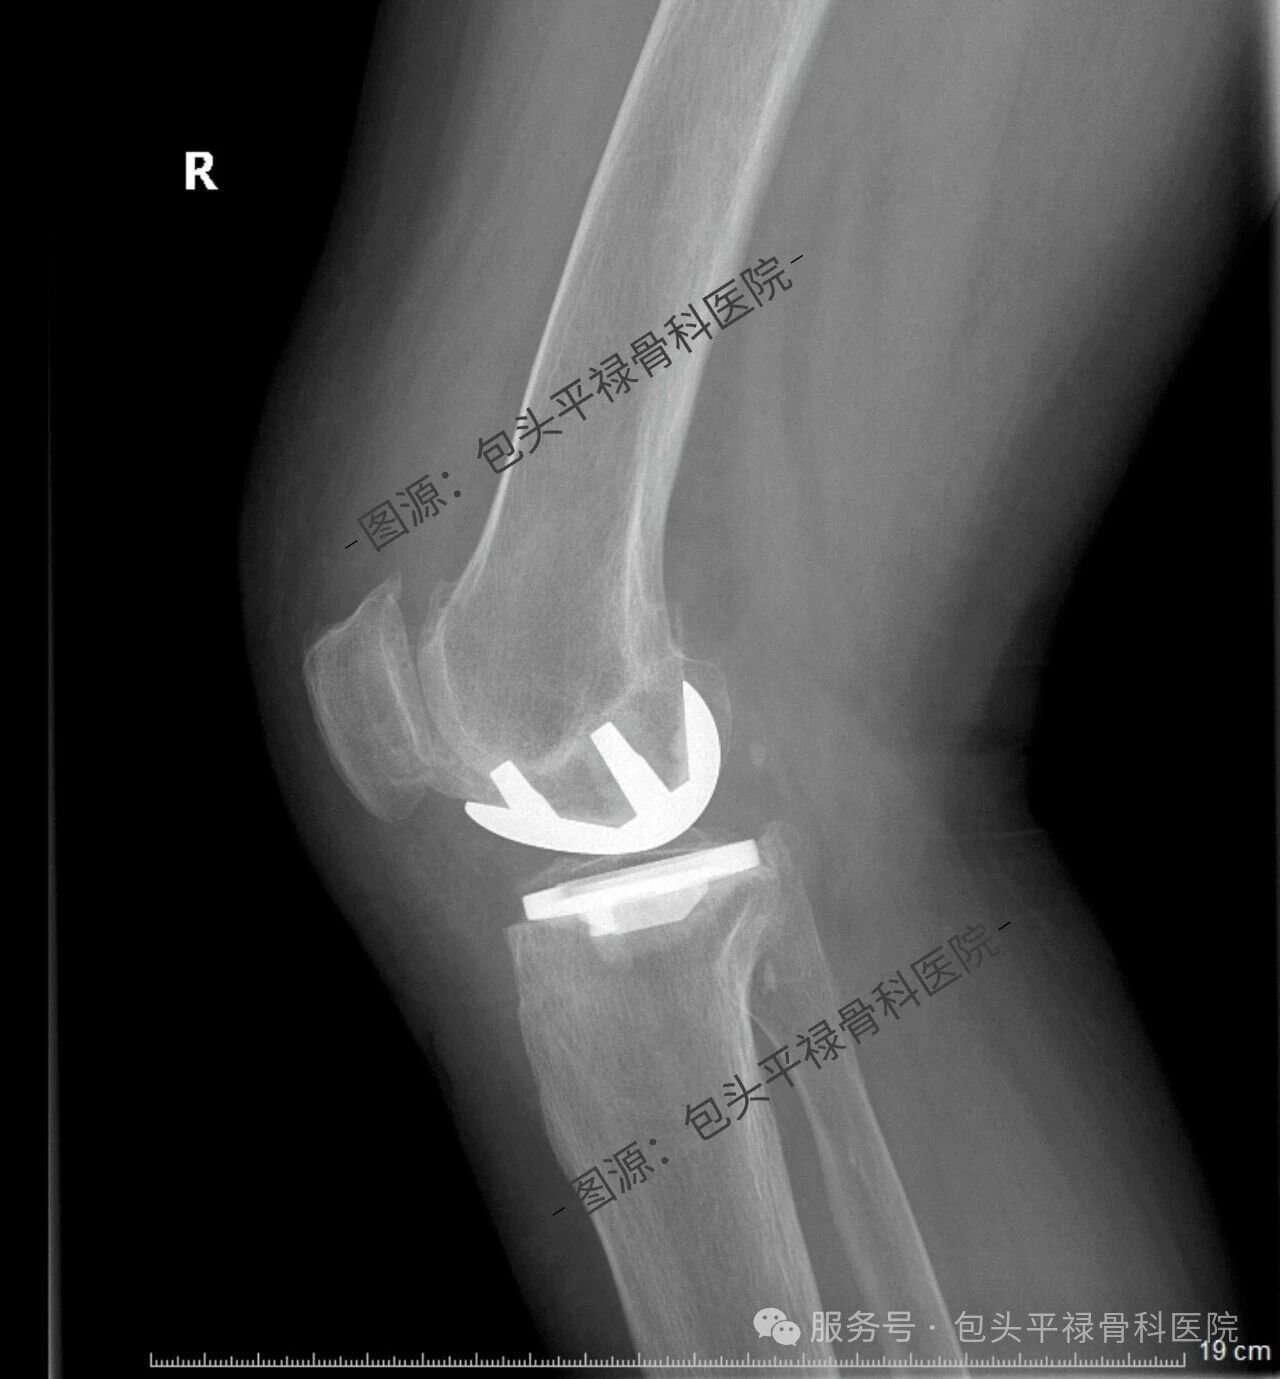

其实,现代医疗技术日趋精准,如果患者的关节炎只局限于膝关节的一个部分(单侧间室),那么TA很可能适合一种更为精准、创伤更小的手术——膝关节单髁置换术。

膝关节单髁置换术相当于“局部翻新”,就是只置换“坏掉房间”的磨损表面,仅将受损的软骨和部分骨质去除,替换为人工假体,而完好的软骨、交叉韧带及其他结构都得以最大程度的保留。

单髁置换术的突出特点是什么?

创伤更小:手术切口短,对软组织损伤小。

出血更少:术中出血量少。

恢复更快:术后当天或次日即可下地,住院时间短,康复速度更快。

感觉更自然:保留了膝关节大部分正常结构和韧带,术后本体感觉更好,上下楼梯、下蹲体验佳。

功能保留更多:术后膝关节活动范围通常更大。